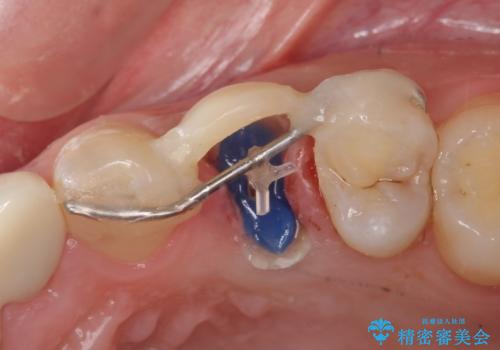

折れた前歯のセラミック修復 根管治療のやり直しもおこなう

前歯が折れてしまい、審美的に大きな問題となっていたため、まずは仮歯にて見た目の回復をしました。

根管治療に関しては、悩んだ結果やり直しを選択され、やや時間はかかってしまいましたが、基礎からしっかりとやり直すことができました。

被せものの種類:PFZ standard